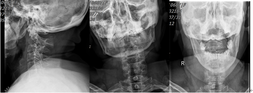

- 68岁的朱大妈骑电动车外出,不慎摔倒伤及头颈部,求诊漳州市中医院骨伤科,行颈椎X线、CT、MRI检查结果为:齿状突骨折伴寰枢椎脱位。该部位的骨折伴脱位对于任何年龄段的患者都是非常危险的,手术难度和风险非常高。寰枢椎钉棒内固定融合术是治疗此类疾病的最佳方案之一,但对手术团队医护人员的要求极高。 图一:颈椎齿状突骨折、骨折移位伴寰枢椎脱位 图二:颈椎齿状突骨折,骨折线前下往后上,属于IIC型 寰枢椎在人体结构中占有极为...发布时间:2020-10-01